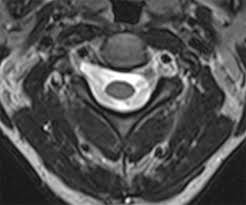

Nerve root pain is variably described as knifelike or aching and is widely distributed projecting to the sclerotome defined as deep structures such as muscles and bones innervated by the root. Lumbar Radiculopathy Nerve Root Compression Lumbar radiculopathy refers to disease involving the lumbar spinal nerve root. The Laser Spine Institute lists sciatica symptoms as pain numbness tingling and burning.

Lumbar radiculopathy is typically caused by a compression of the spinal nerve root. Typically root pain is aggravated by coughing sneezing and straining at stool actions that require a Valsalva maneuver and raise intraspinal pressure. Loss of strength reflex and sensation occurs in the territory of the compressed root. There is a significant volume of literature that would point to the neural tissues themselves as the most logical structures for future research that attempts to interfere with the natural history of this disease from the standpoint of pain. It is defined as sudden usually unilateral severebrief stabbing lancinating recurring pain in the distribution of one or more branches of the Vth cranial nerve Trigeminal neuralgia also known as prosopalgia or fothergills disease is aneuropathic disorder characterized by episodes of intense pain in the face originating from trigeminal nerve. Herniated disc causing a single nerve root compression leg pain back pain. An estimated 20 million Americans suffer from peripheral nerve damage aka.